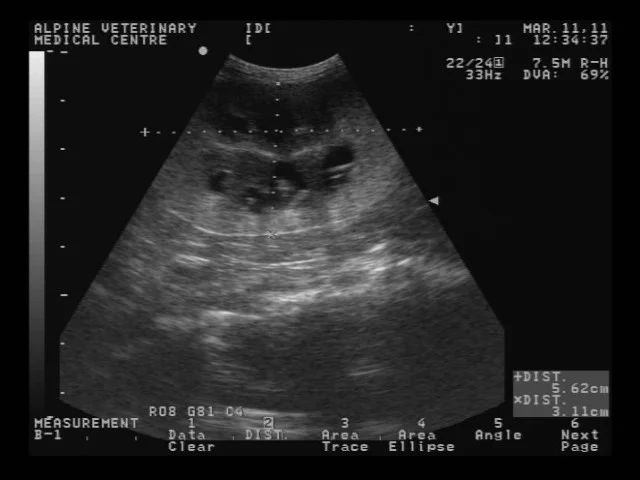

ultrasound of a dog kidney